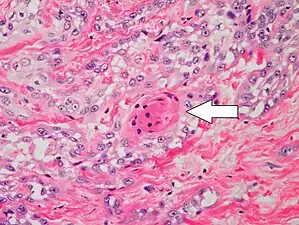

Well-differentiated (and yet invasive) SCC, showing prominent keratinization and may form “pearllike” structures where dermal nests of keratinocytes attempt to mature in a layered fashion. Well-differentiated SCC has slightly enlarged, hyperchromatic nuclei with abundant amounts of cytoplasm. Intercellular bridges will frequently be visible.[33]

Poorly differentiated, where attempts at keratinization are often no longer evident. This is a clear-cell squamous cell carcinoma. The dysplastic cells here infiltrate in cords through the dermis. Poorly differentiated SCC has greatly enlarged, pleomorphic nuclei demonstrating a high degree of atypia and frequent mitoses.[33]

Poorly differentiated clear-cell squamous cell carcinoma. For this type of SCC, immunostains will likely be required to classify it unless other areas of the tumor show obvious squamous cell features such as seen here (arrow).